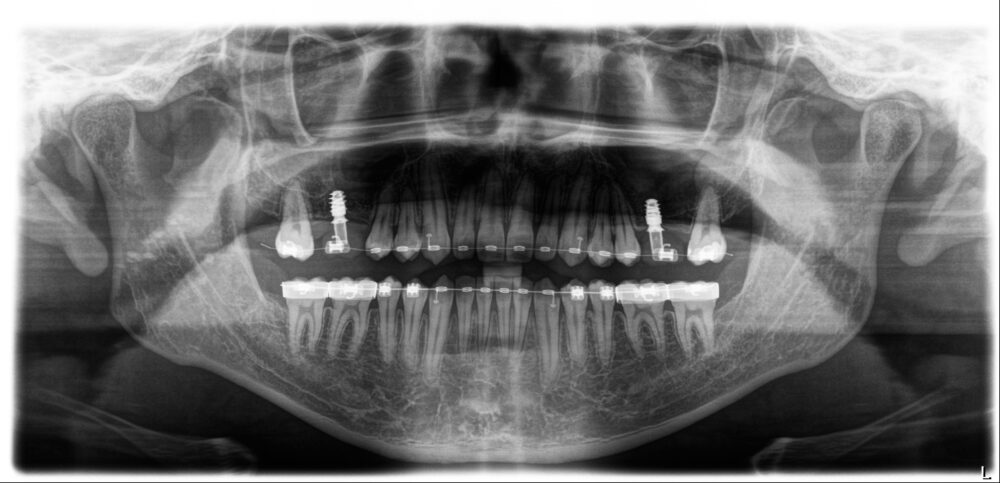

矯正治療開始より1年10ヵ月後、両側下の5番目にインプラントOpeを行い、3ヵ月後プロビジョナルレストレーション(暫間修復歯)を入れることになりました。

プロビジョナルレストレーション(暫間修復歯)作製のためのスキャンを行い、技工士にデジタルデザインを依頼したところ、左右対称のデザインを実現するには、一部矯正治療の追加が必要であると判断し、右上の奥歯(計8本)のみブラケット治療を行うことになりました。

ブラケット治療開始から8ヵ月、今回の治療目的が達成していることを確認し、再びアライナー治療を再開しました。

治療再開から6ヵ月、奥歯8本に予定していた補綴治療(セラミックの詰め物や被せ物)を行い、治療終了です。

治療前気になっていた「出っ歯」が気にならなくなり、治療前は歯が抜けていない方ばかりを使っていた片方噛みをしなくなったと審美的にも機能的にも仕上がりを喜んでおられます。

治療期間 3年3か月(プレオルソ・アライナー・ブラケット)

費用 2,570,000円(税別)